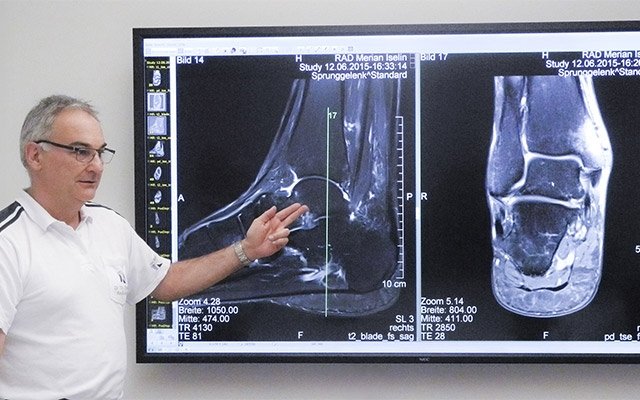

With demographical change and the rise of medical competence centres, providing clinical healthcare is very specialized and professional, but also offers more and more challenges. People live longer and their mobility is decreasing. They can’t use cars on their own and public transportation is challenging for them – especially when in medical need. With the NEC InfinityBoard – our all-in-one meeting room solution – and a decent healthcare partner network, Sharp meets the special requirements of the healthcare industry. Not only is the NEC InfinityBoard meant to be part of the MDT Room to enhance collaborative working and get remote participants on board, but also the Sharp solution enhances collaboration and consultancy with operating surgeons.

With the digitalisation of Operating Rooms, the work of surgeons and the whole team around becomes more and more efficient. Not only can surgeries inside the OR be supported by visualisation on Large Format Displays, but also video streaming makes an impact. Sharp, together with Kramer AV, supports the connection of OR’s to the outside world!

Live surgery and telestration are important, especially in teaching hospitals. While the surgeon operates, a head camera is live-streaming images to a bigger audience. In this way, many student surgeons can participate.